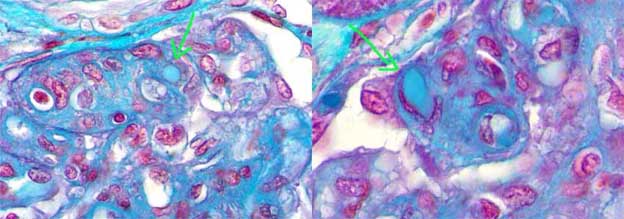

Figure 2. Amyloid deposits highlight with the trichrome staining (blue), like areas of mesangial acellular widening (arrows). (Masson’s trichrome, X400).

Figure 3. In some cases these deposits are more prominent in capillary walls, giving a thick and rigid aspect to them. The arrow indicates a capillary wall in which the deposits adopt a perpendicular disposition to this wall (see also Figure 4). (Masson’s trichrome, X400).